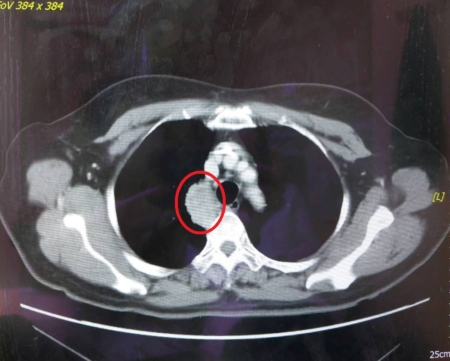

【大紀元2025年04月30日訊】(大紀元記者陳文敏台灣苗栗報導)62歲的陳女士因慢性咳嗽及背痛到醫院就醫,診斷為第四期肺腺癌,由於她的常見致癌突變基因檢測為陰性,無法使用目前臨床效果最好的EGFR標靶藥物治療,液態切片次世代基因檢測也未能找到相關突變基因及有效的藥物治療,加上使用第一線及第二線的化學治療皆出現抗藥性及副作用。因此,在醫療團隊的建議下,接受微創手術取腫瘤組織做次世代定序基因檢測,終於找到罕見的Met突變基因的標靶藥物治療,讓病人有重生的希望,同時透過健保給付,幫助病人及家屬減輕治療費用的負擔。

大千綜合醫院醫療副院長暨胸腔內科醫師謝為忠表示,過去面對病人在第一線治療出現抗藥性時,只能嘗試新藥物或是沒使用過的其他藥物,卻會有費用昂貴且效果不明的缺點,對病人及家屬都是很大的負擔。現今,透過抽血或取腫瘤組織做次世代定序基因檢測(NGS),可判斷出病人癌細胞的突變基因,協助醫師擬定適合的治療策略,精準選擇用藥,並針對副作用調整劑量,進而達到更好的治療效果,讓每位病人獲得最適切的個人化治療。